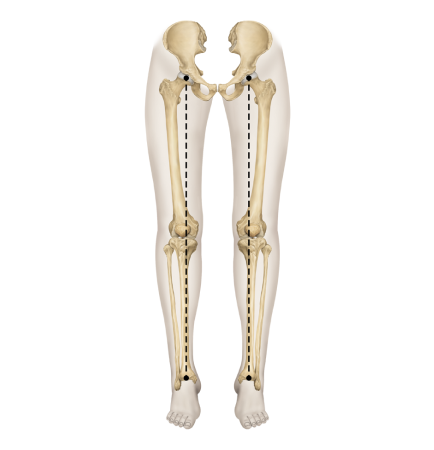

X다리

• 무릎이 안쪽으로 모이면서 다리 축이 변형됨

• 체중 부하가 다리 바깥쪽에 집중되어 외측 관절의 압력증가로

무릎 통증, 불안정성, 관절 손상을 유발할 수 있음

• 허벅지 바깥쪽 근육이 과도하게 발달하고 안쪽 근육이 약화되면 외반슬이 진행

다리의 각도와 회전에 따라

경사형 휜다리

발의 변형이나 요족 및 걸음걸이 이상으로 무릎에 비정상적인 힘이 작용하며 생김

회전형 휜다리

고관절과 무릎이 내회전되어 발,발목 변형 동반되는 경우가 많고, 척추와 골반이 함께 틀어짐

복합형 휜다리

전면은 회정형 원다리처럼 보이나 경사형과 회전형 원다리 특징을 모두 가진 형태

특발형 휜다리

특발성측만증을 동반하거나 사고로 인한 경우 또는 다리 길이 차이 등 구조적 문제를 동반

사람마다 얼굴이 다르듯 휜다리도 다양한 패턴이 있습니다.

무릎 정상패턴과 신전패턴 2가지

경사 / 회전 / 복합 / 특발형 4가지

평발 / 요족 / 정상발 3가지

골반부정렬 6가지

총 144가지 타입